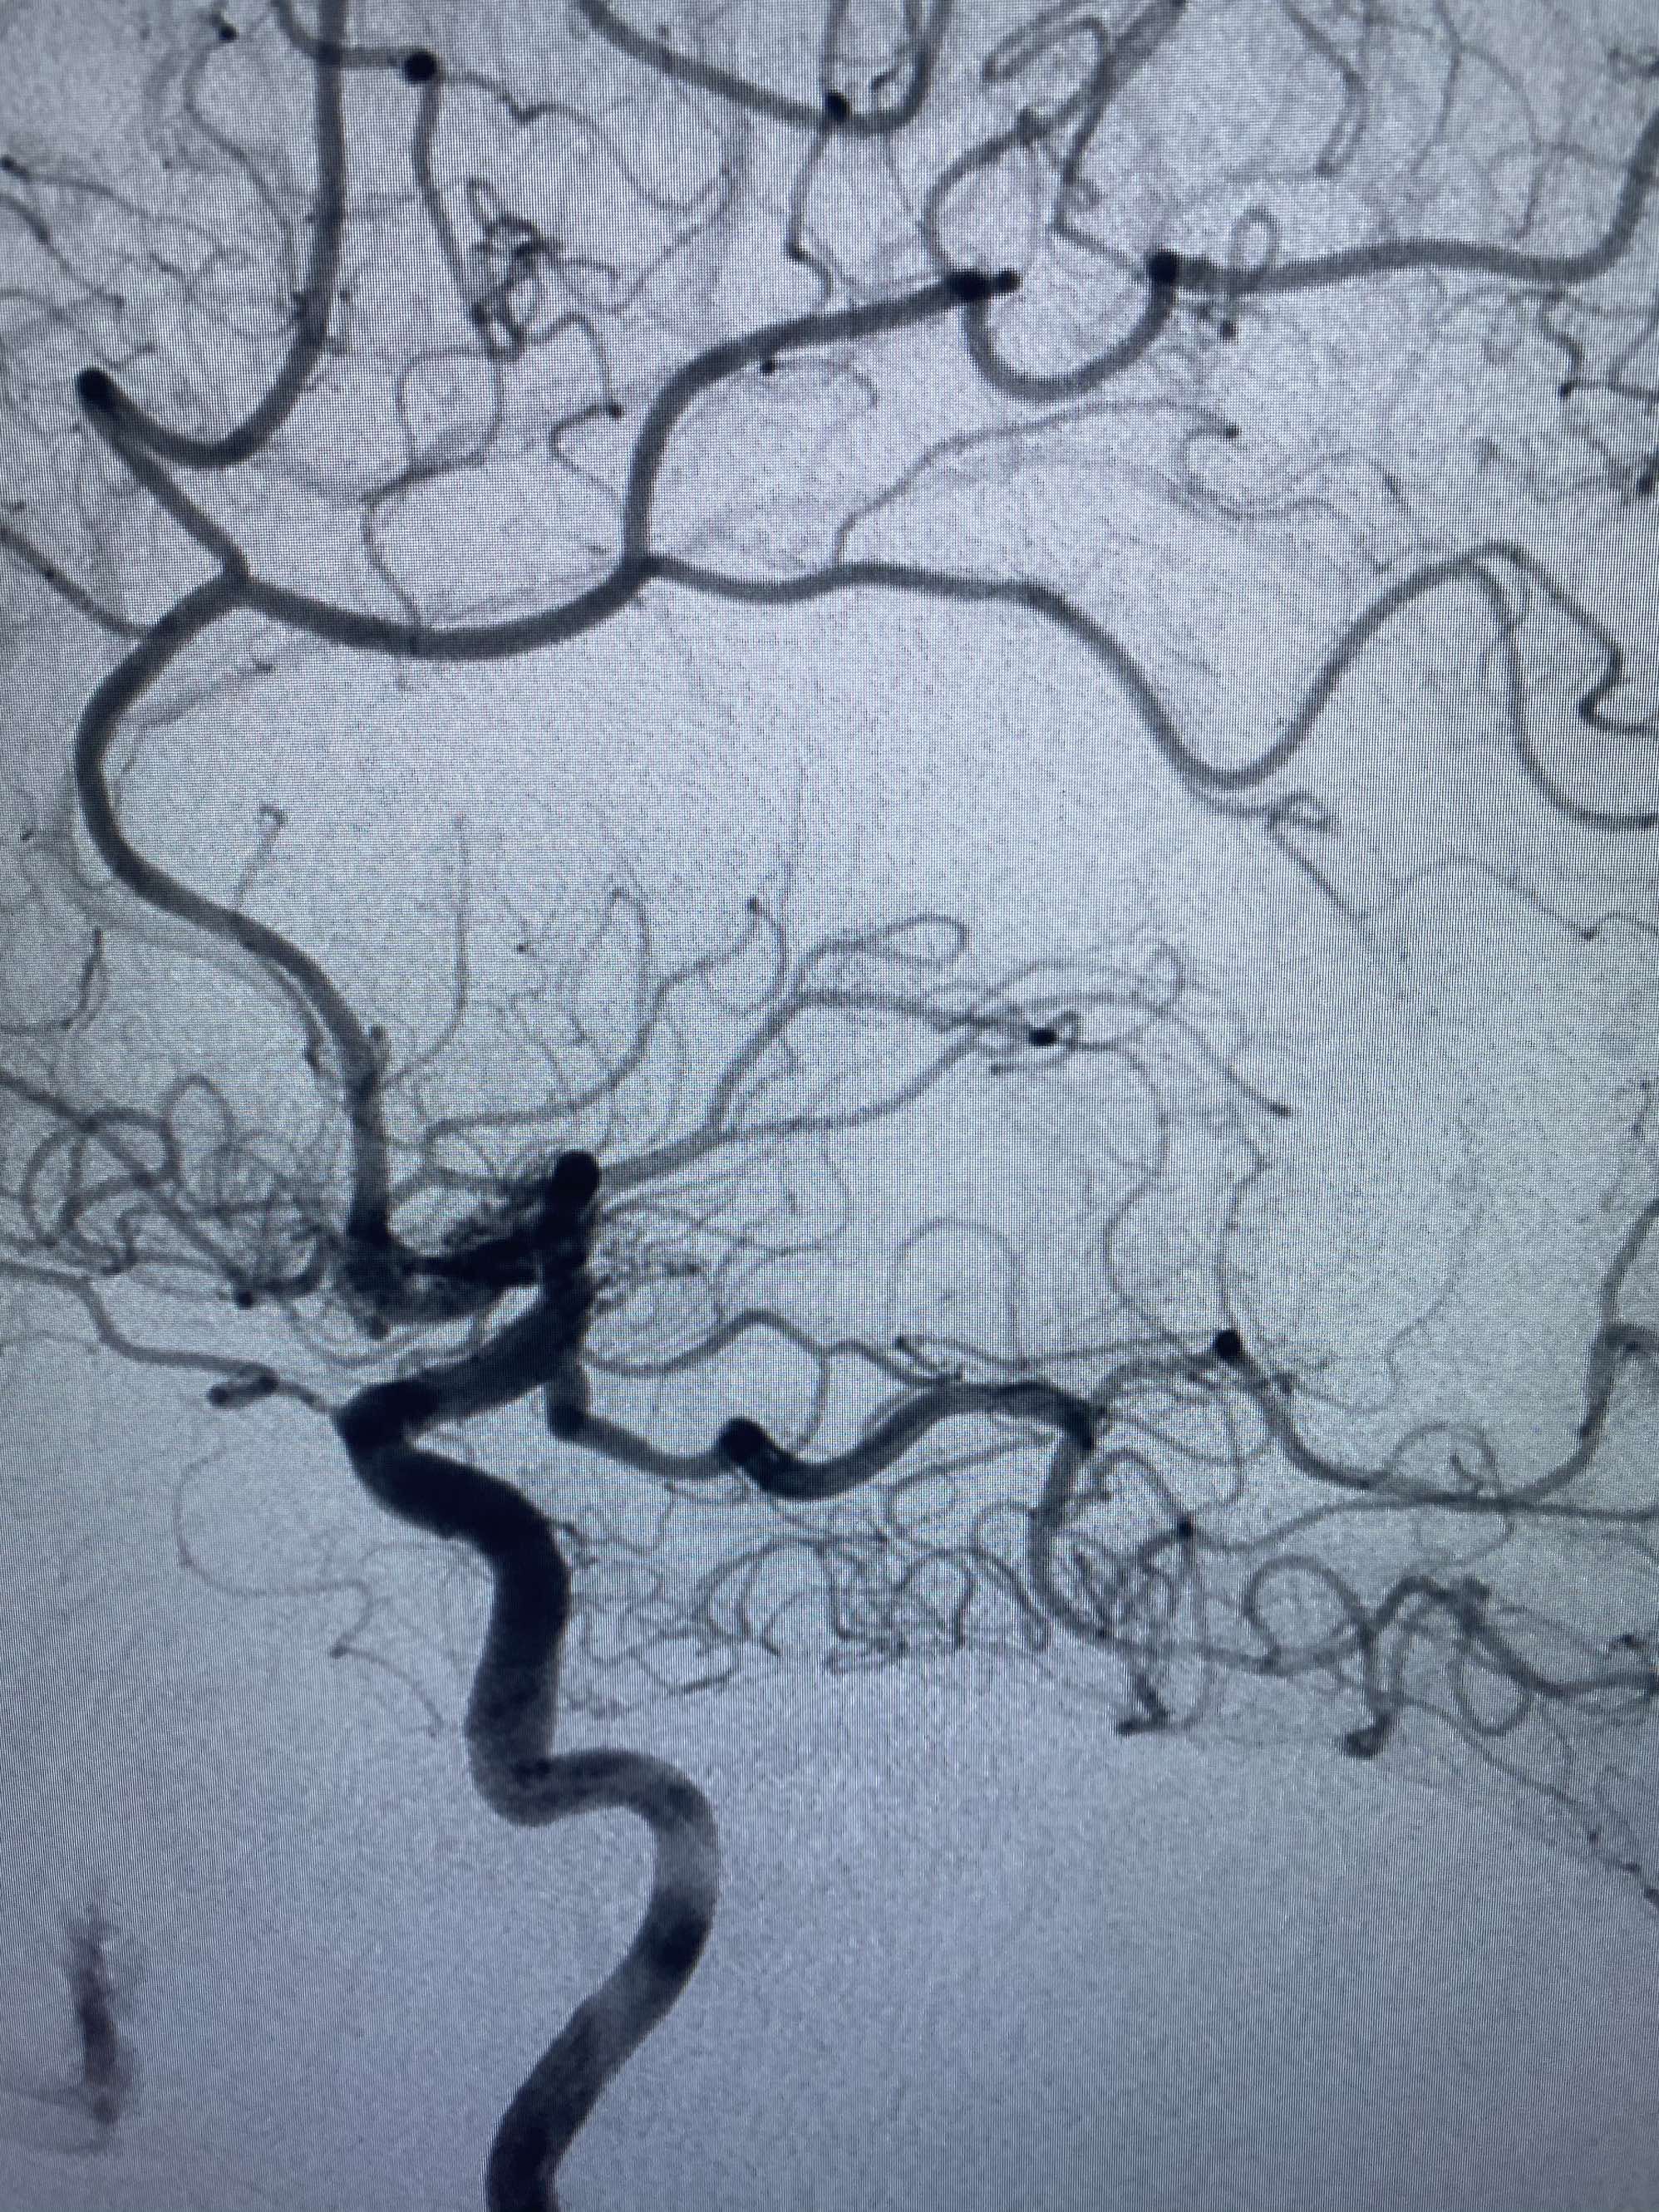

MLS,M79Y,sah,双侧MCA烟雾病,Heubner返动脉瘤,前交通段开窗,细支发出Heubner返动脉,瘤颈细长,瘤颈口比微导管细,弹簧圈2mmx3cm“隔山打牛”填塞治愈,Heubner返动脉保留。

该患者术后2天观察神志清楚,四肢活动正常。

Heubner返动脉是由大脑前动脉A1末端发出的豆纹动脉,由于走形和A1段相反,故称Heubner返动脉,该动脉梗塞可能引起尾状核头梗塞,引起偏瘫和面瘫,便身震颤等症状。